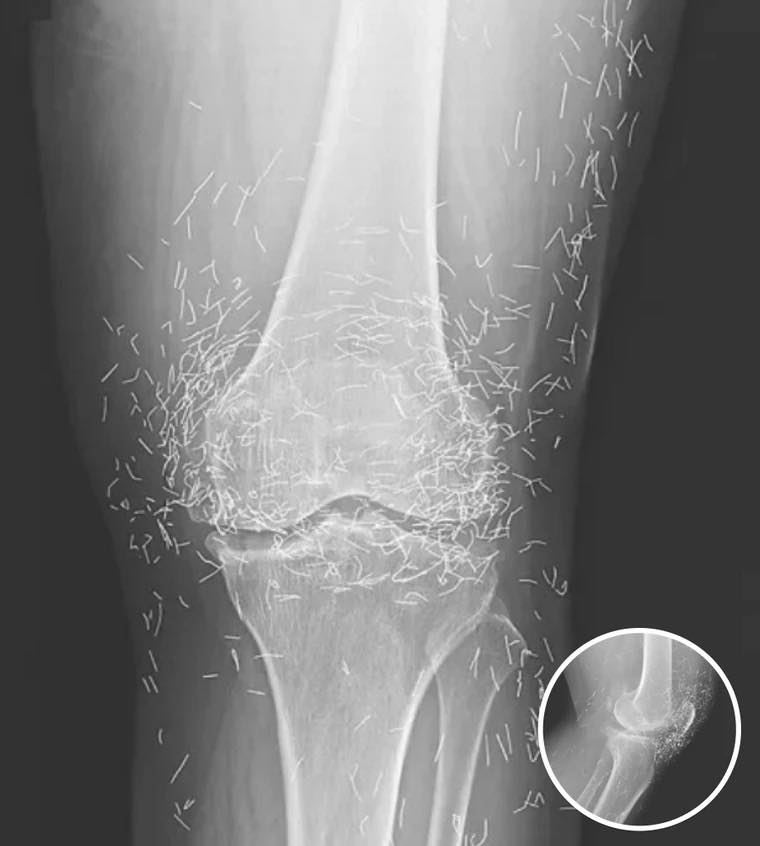

A routine X-ray revealed an unexpected surprise when doctors examined the knees of a 65-year-old woman suffering from severe joint pain. What they found was nothing short of astonishing — hundreds of tiny gold needles embedded deep in her tissue.

There are other complications as well. Needles lodged in tissue can interfere with medical imaging. “They can obscure parts of the anatomy on an X-ray,” Guermazi noted. Even more alarming, patients with metal fragments in their bodies should never undergo an MRI, as the magnetic force could cause the needles to move — potentially puncturing blood vessels and causing life-threatening damage.

A X-ray of the patient’s knee showing acupuncture needles embedded in the tissue, Photo Credit: Reddit

As for the South Korean woman, her case was recently documented in the New England Journal of Medicine. While the needles may have been intended to help, her X-rays tell a cautionary tale about the potential risks of extreme alternative therapies.